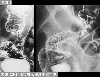

Posted by: Tokyo Pref., Cooperative study between National Cancer Center and Kyushu Cancer Center

Date of entry 2014/02/28

Number of image 47